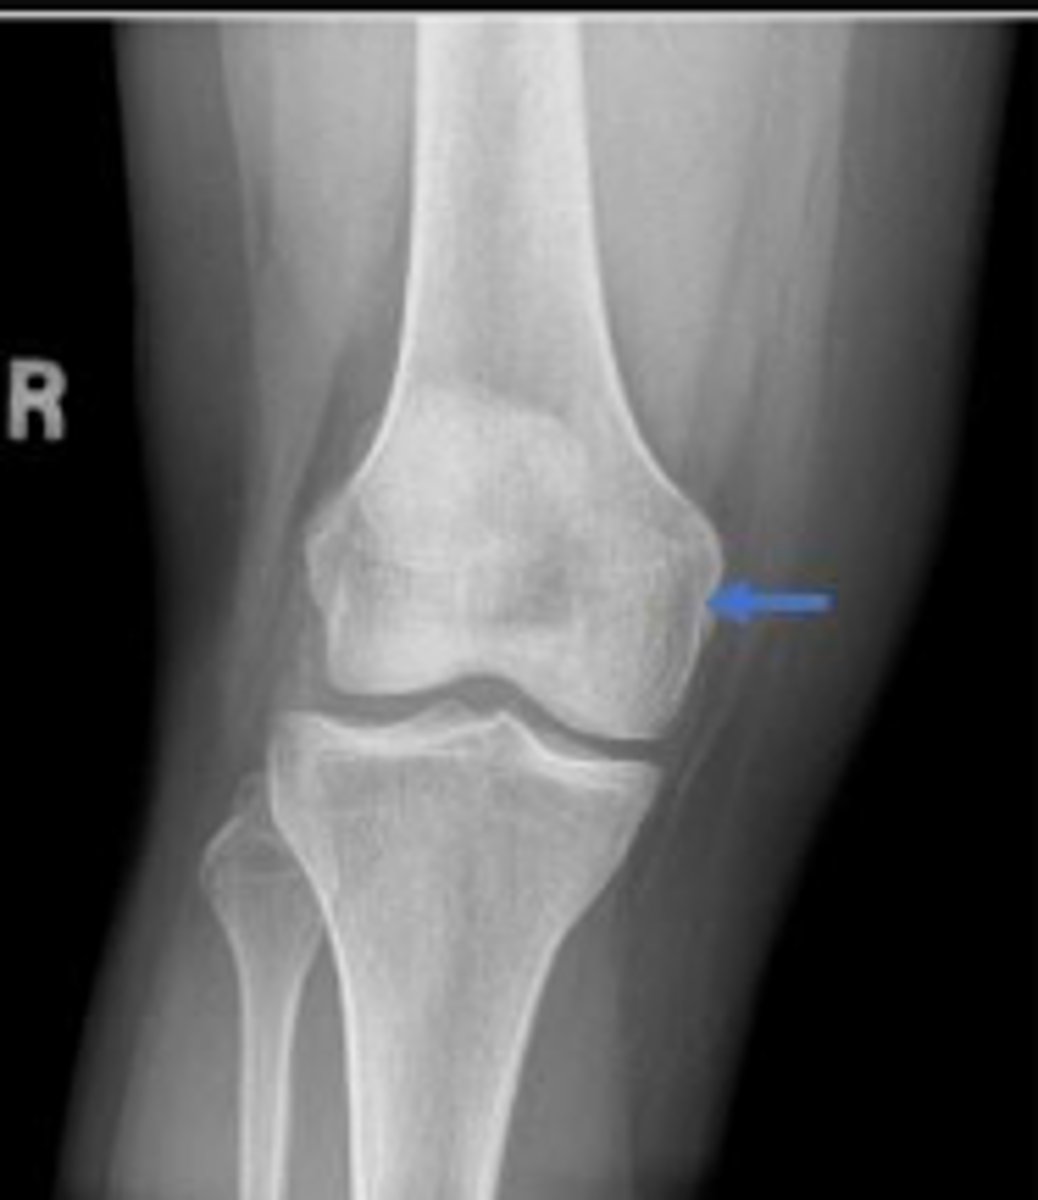

Medial epicondyle of the right femur

What is the arrow pointing to?

Medial condyle of the right femur

What is outlined?